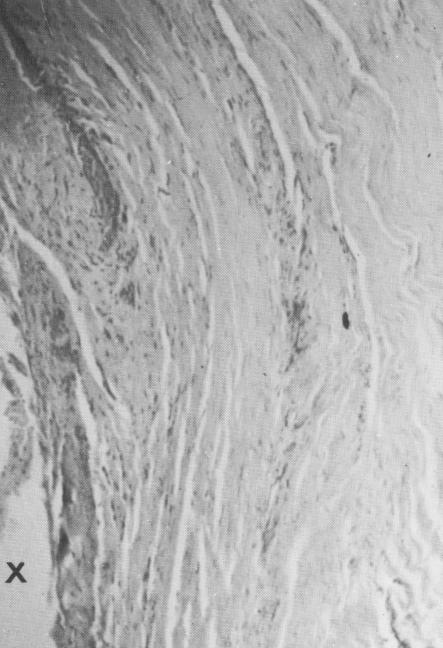

Fig. 4-50. Small area of calcification (arrow) near the periphery of the soft tissue strip.

2 Vent plant implant site shows calcified tissue at soft tissue periphery